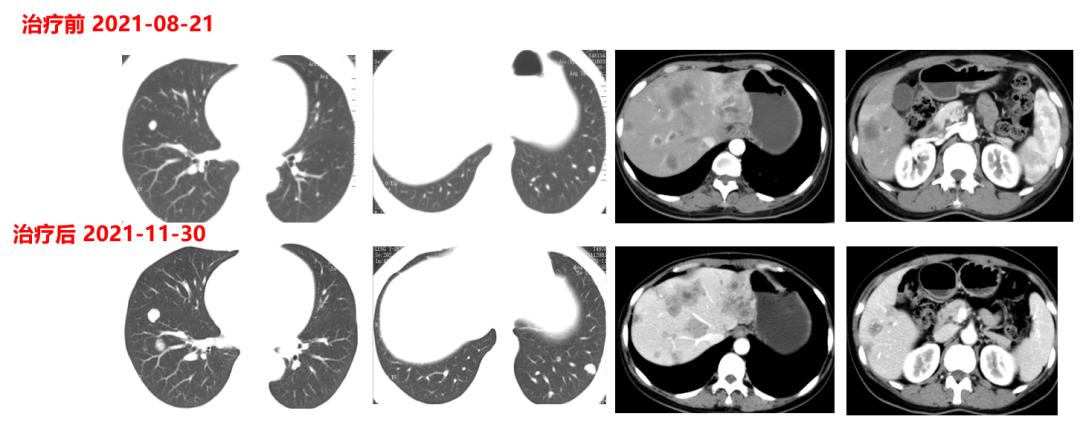

一线治疗(2021-4-17至2021-11-30,PFS:6月余):

于2021.04.17行“FOLFOX6”方案化疗1周期,行“奥沙利铂”化疗时,出现严重过敏。因患者基因状态为RAS,BRAF野生型,第2周期始给予“FOLFIRI+西妥昔单抗”,在治疗过程中,肿瘤标志物持续下降,影像学也显示肝脏病灶明显缩小。疗效评价PR,在2021-09-25在局麻DSA下行“肝动脉造影并化疗灌注栓塞术”。

肿瘤初次进展(2021-11-30)

患者于2021年11月30号复查时,肺上病灶增大增多,肝脏病灶稍增大,肿瘤标志物增高,整体疗效评价PD,考虑一线治疗进展。

二线治疗(2021-12至2022-8-3,二线PFS:7月余):

于2021-12-03、2021-12-27给予伊尼妥单抗+吡咯替尼方案治疗2周期。2022.1.19始给予患者伊尼妥单抗+吡咯替尼+替雷利珠单抗治疗,两周期,四周期时的疗效评估可以看到,肺上病灶明显缩小,甚至有的病灶消失,肿瘤标志物也在持续下降。